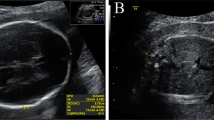

A Pedigree of the non-consanguineous Chinese family. B–D Fetal II-5 ultrasound findings at 25 weeks of gestation showing the umbilical cord cysts. (B), abnormal conus medullaris morphology (C), and thickened heel subcutaneous tissue (D). E–K Fetal II-5 magnetic resonance imaging showing abnormality of the scrotum (E–F), thoracic scoliosis (G–H), abnormal conus medullaris morphology (I), hand clenching (J), and rocker bottom foot (K)

Subsequently, fetal ultrasound of the fifth pregnancy (II-5) revealed increased nuchal translucency (NT: 8.8 mm), hand clenching, adducted thumb, absence of stomach bubble on fetal sonography, polyhydramnios, umbilical cord cysts, abnormal conus medullaris morphology, and thickened heel subcutaneous tissue (Fig. 1B–D) at 25 weeks’ gestation. Magnetic resonance imaging (MRI) showed abnormality of the scrotum, thoracic scoliosis, abnormal conus medullaris morphology, hand clenching, rocker bottom foot, fetal immobility, and subcutaneous oedema (Fig. 1E–K). The fetal and the couple's karyotypes were normal. Based on the multiple malformation outcomes, the pregnancy was terminated 3 weeks later. Whole exome sequencing analysis was performed using the fetal umbilical cord and parents’ blood. Unfortunately, the II-5 muscle samples were not retained for histological studies.